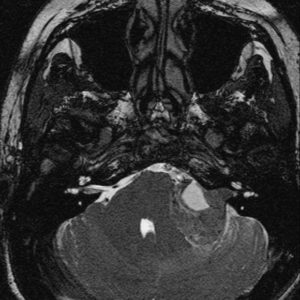

U dây VIII

Lượt xem: 162» 02-03-2019 -

U dây VIII

Lượt xem: 132» 24-11-2018 -

U dây VIII

Lượt xem: 130» 24-11-2018 -

U dây VIII

Lượt xem: 153» 24-11-2018 -

U dây VIII

Lượt xem: 147» 24-11-2018 -

U dây VIII

Lượt xem: 117» 24-11-2018 -

U dây VIII

Lượt xem: 149» 24-11-2018 -

U dây VIII

Lượt xem: 143» 24-11-2018 -

U dây VIII

Lượt xem: 158» 24-11-2018